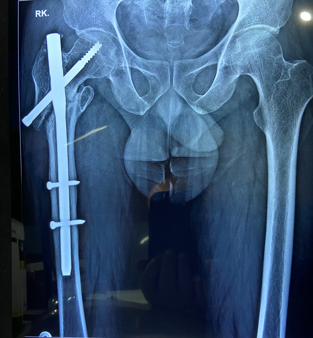

In a series of delayed union with internal fixation over 47 patients regardless of the fracture sites communition or inadequate fixation, had union in all patients including a case of infected nailing of femur. These patients had reported to Dr. S S Jha three to seven months after internal fixation at other centers. None of these patients were willing to submit themselves for further surgical intervention. Teriparatide 20mcg daily through subcutaneous route was started in all patients with adequate supplementation of vitamin D and calcium. Evident radiological bony union was perceptible after three months with clinical improvement in the initial presenting symptoms of the patients and the osseous consolidation was invariably observed radiologically within four to six months. It was only in six patients that Teriparatide was continuously used for one and half years for reasons of general debility, elderly age and osteoporosis. Radiographs of three difficult cases are being displayed from the series.

Case 2([Figure 10], [Figure 11])

Case 3([Figure 12])

- Case 2([Figure 10], [Figure 11])

- Case 3([Figure 12])